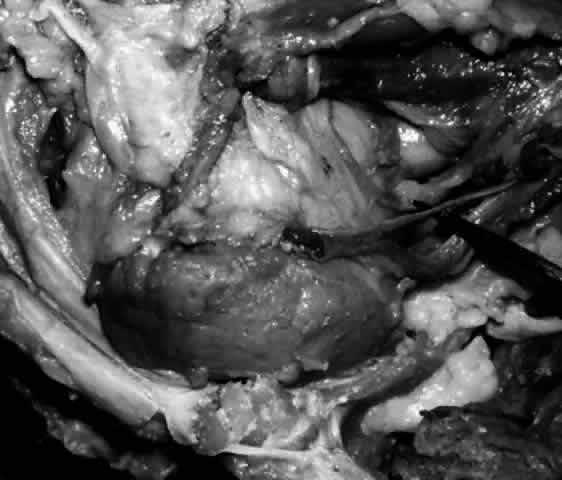

The main lacrimal gland resides in the superotemporal orbit, partially within a shallow bony fossa in the lateral angular process of the frontal bone (fossa glandula lacrimalis). The gland is situated between the eyeball below and the curved orbital wall above, giving it a somewhat compressed and curved shape. It may extend inferiorly to the lateral canthal tendon. The lateral horn of the levator aponeurosis crosses the gland anteriorly, separating it into a larger superior or orbital lobe and a smaller inferior or palpebral lobe (Fig. 2). The division is incomplete because the larger orbital lobe is connected to the smaller palpebral lobe posteriorly by a bridge of glandular tissue, draining tubules, and Müller's muscle, which is attached to the underside of the levator muscle and aponeurosis. The lacrimal gland is surrounded by fibrous tissue that is attached superiorly to the periosteum of the frontal bone and inferiorly to the orbital portion of the zygomatic bone.1

Fig. 2. With the roof and lateral wall of the left orbit removed, this cadaver dissection demonstrates the orbital lobe (black arrow) and the palpebral lobe (white arrow) separated by the lateral horn of the levator aponeurosis (pointer).

The almond-shaped orbital lobe (see Fig. 2) represents approximately 65% to 75% of the gland and measures 20 mm long × 5 mm thick × 12 mm wide.2 Its sharp anterior border rests behind the superior orbital rim and is covered by the orbital septum (Fig. 4) and a portion of the temporal aspect of the central preaponeurotic fat pad (Fig. 5). Posteriorly, its rounded border is supported by a large superotemporal fat pad at the plane of the posterior pole of the globe.3 The convex superior surface is suspended from the periorbita of the lacrimal gland fossa of the frontal bone. The inferior border is convex and attached to the sheath of the levator aponeurosis. Its lateral border is smooth and convex in contour with the bony fossa.

The inferior or palpebral lobe of the lacrimal gland (see Fig. 2) represents approximately 25% to 35% of the gland and lies beneath the levator aponeurosis in the subaponeurotic space. It extends anteriorly beyond the orbital margin to lie in the lateral portion of the superior fornix. The palpebral lobe can be seen through the conjunctiva when the eyelid is elevated or everted (Fig. 6).